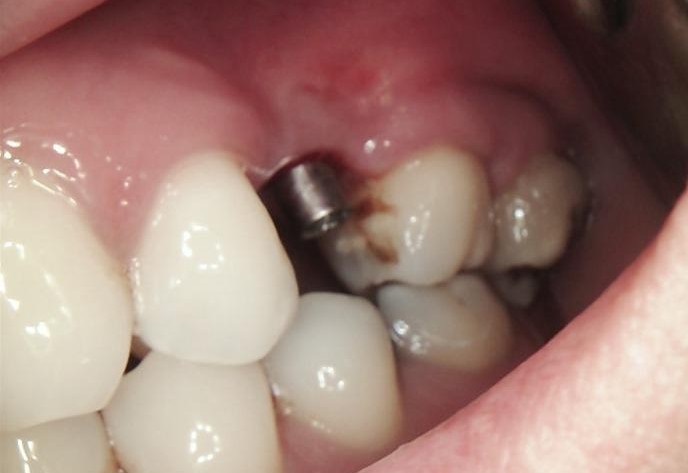

INITIAL STATE

Clinical and radiographic examination revealed a failed implant with signs of periimplant tissue compromise. Intraoral evaluation demonstrated inadequate soft tissue quality and unfavourable conditions for immediate restoration. CBCT imaging was performed to assess bone volume, implant position, and anatomical limitations prior to treatment planning.